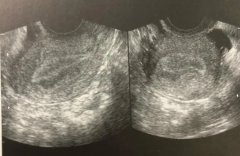

胚胎着床和子宫内膜的关系? 无论是自然受孕还是做试管,子宫环境都直接影响到妊娠成功率。好的子宫环境能提供胚胎成功着床的必要条件,内膜如果厚度正常、结构正常、血流丰富,就